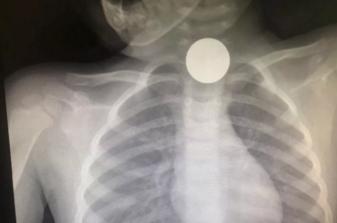

(一枚硬币卡在食管上端)

近日,家住宁波鄞州的2岁小女孩妞妞,在误吞硬币3天后才被家长发现异常,送到宁波浙江大学明州医院儿科检查时,妞妞的食管已出现溃疡,并有食管穿孔。

“据家长描述,患儿近2天饭量明显变少,抗拒吃东西,一吃就吐就哭,他们以为是咽喉炎之类的便决定观察看看。”施主任说,“看到情况一直不好转,就送来医院检查,结果拍片提示在食管上端卡着一枚硬币。”